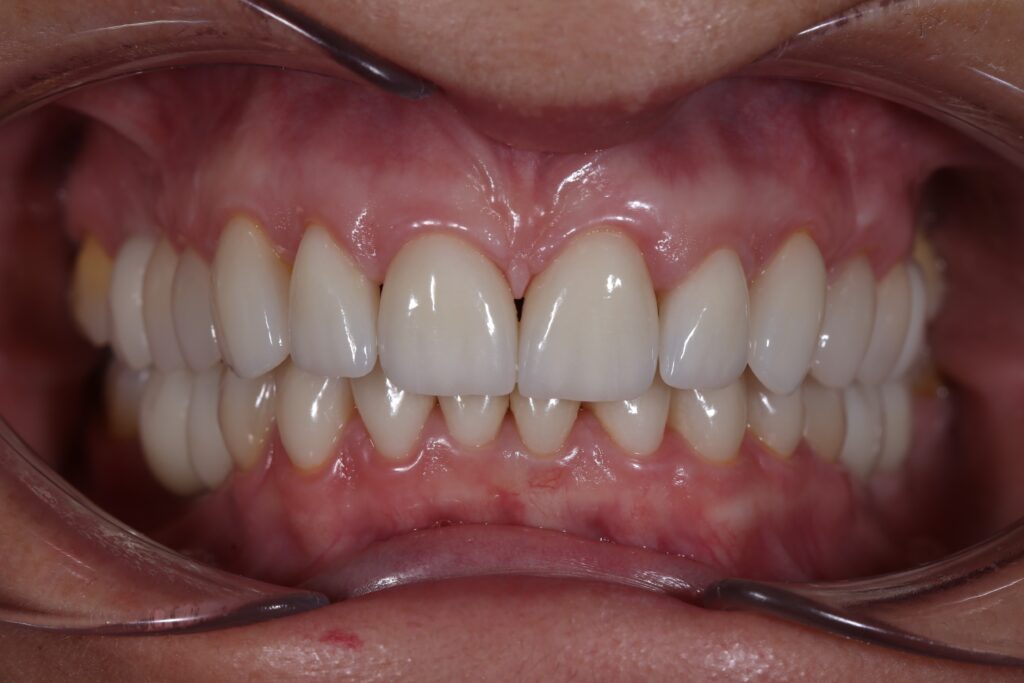

Этап имплантации и протезирования и результаты

Затем были установлены имплантаты Megagen AnyOne.

Спустя 3 месяца после установки имплантатов была произведена замена несостоятельных реставраций и пломб для избежания развития вторичного кариеса под винирами и коронками.

Сделано препарирование зубов на верхней и нижней челюстях с контролем глубины (0.7-0.8 мм) под керамические реставрации. Сняты оттиски с имплантатов.

Установлены временные виниры и коронки из пластика. Спустя 26 дней были зафиксированы керамические виниры и коронки на своих зубах и циркониевые коронки на имплантатах.

Результаты